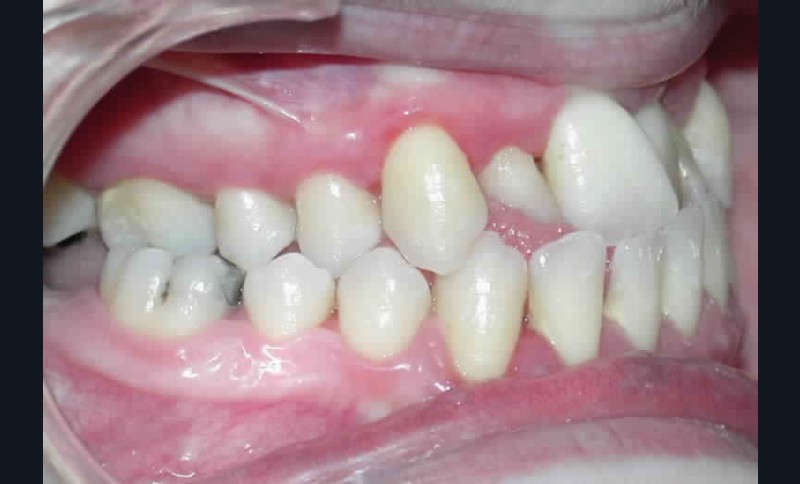

Cette patiente est venue consulter pour son occlusion inversée et ses importantes malpositions dentaires antérieures associées à la perte d’une dent et à des problèmes parodontaux.

• Malocclusion de classe III d’Angle par rétroalvéolie maxillaire,

• endoalvéolie maxillaire avec occlusion inversée antérieure et bilatérale,

• infraclusion incisive,

• fortes malpositions des incisives supérieures (dont 22 qui est en rotation axiale disto-palatine de 90°), • dysharmonie dento-dentaire (12 en « grain de riz » est aussi en rotation marginale disto-palatine de 45°),

• anomalie de la forme d’arcade maxillaire, 47, 18 et 28 sont absentes. (fig. 1 à 8), 48 est positionnée très postérieurement, quasiment au niveau de la branche montante (fig. 9 et 11).